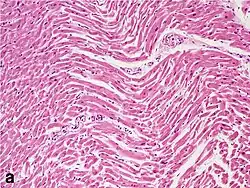

Under the microscope, myocardial infarction presents as a circumscribed area of ischemic, coagulative necrosis (cell death). On gross examination, the infarct is not identifiable within the first 12 hours.[20]

Although earlier changes can be discerned using electron microscopy, one of the earliest changes under a normal microscope are so-called wavy fibers.[21] Subsequently, the myocyte cytoplasm becomes more eosinophilic (pink) and the cells lose their transversal striations, with typical changes and eventually loss of the cell nucleus.[22] The interstitium at the margin of the infarcted area is initially infiltrated with neutrophils, then with lymphocytes and macrophages, who phagocytose ("eat") the myocyte debris. The necrotic area is surrounded and progressively invaded by granulation tissue, which will replace the infarct with a fibrous (collagenous) scar (which are typical steps in wound healing). The interstitial space (the space between cells outside of blood vessels) may be infiltrated with red blood cells.[20]

These features can be recognized in cases where the perfusion was not restored; reperfused infarcts can have other hallmarks, such as contraction band necrosis.[23]